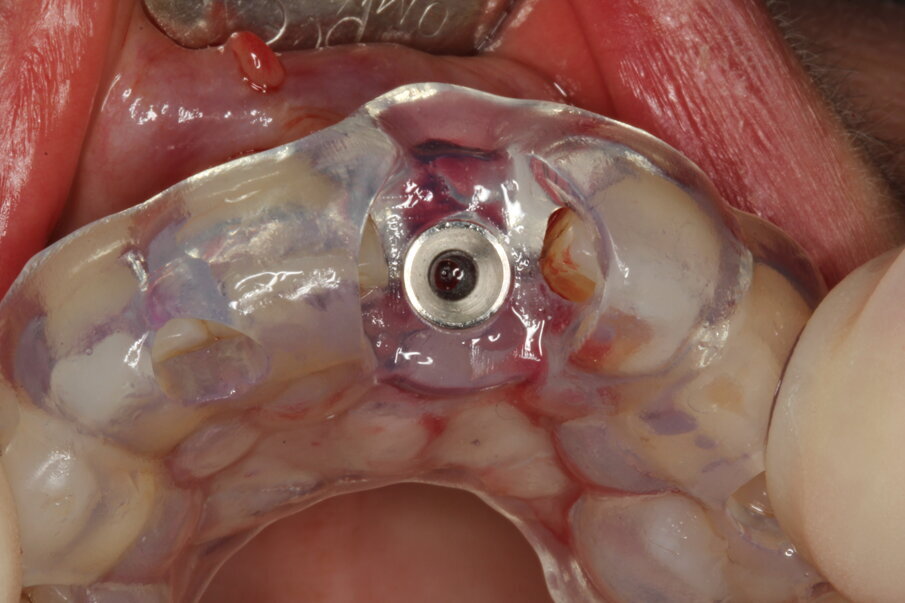

Local anaesthesia was performed with 2% mepivacaine with 1:100,000 adrenaline. Preventative antibiotic therapy with amoxicillin (1 g, b.d. for five days) was prescribed, aided by use of a 0.2 % chlorhexidine mouthrinse three times a day for one minute. The tooth was extracted and the sulcular epithelium removed with diamond burs. The milled surgical template (Figs. 12 & 13) served as a guide for the first 2 mm diameter pilot drill (Fig. 14). Thus, the planned depth, position and angulation of the osteotomy were obtained. The drill sequence was completed freehand, using tapered 3.0 and 3.4 mm drills. A Neoss Pro- Active Tapered Implant of 4 mm in diameter and 13 mm in length was inserted flush with the mesial/palatal/distal bone, motor driven up to a torque of 50 Ncm and then with a manual wrench (Fig. 15). The correct position of the internal hex was verified by checking the references on the implant driver, which ideally points in the buccal direction. Resonance frequency analysis with Penguin RFA (Integration Diagnostics Sweden) determined an ISQ value of 73/76. At this stage, a Neoss Esthetic Healing Abutment with a ScanPeg was connected to the implant (Fig. 16). A flap was then raised after a vertical incision of the frenulum and the expected buccal exposure of the implant neck was evident. Autogenous bone harvested from the drills was positioned directly on the implant surface (Fig. 17), followed by a bone substitute on top of it and on the buccal cortical bone (Fig. 18). This material was covered with a resorbable membrane (Fig. 19). The mobilised flap was then repositioned by rotating it coronally and fixed with single sutures (Fig. 20). The removable partial denture was adapted and delivered (Fig. 21). An immediate postoperative CBCT scan of 60 x 60 mm was performed, and it confirmed a perfectly centred implant position (Figs. 22 & 23).